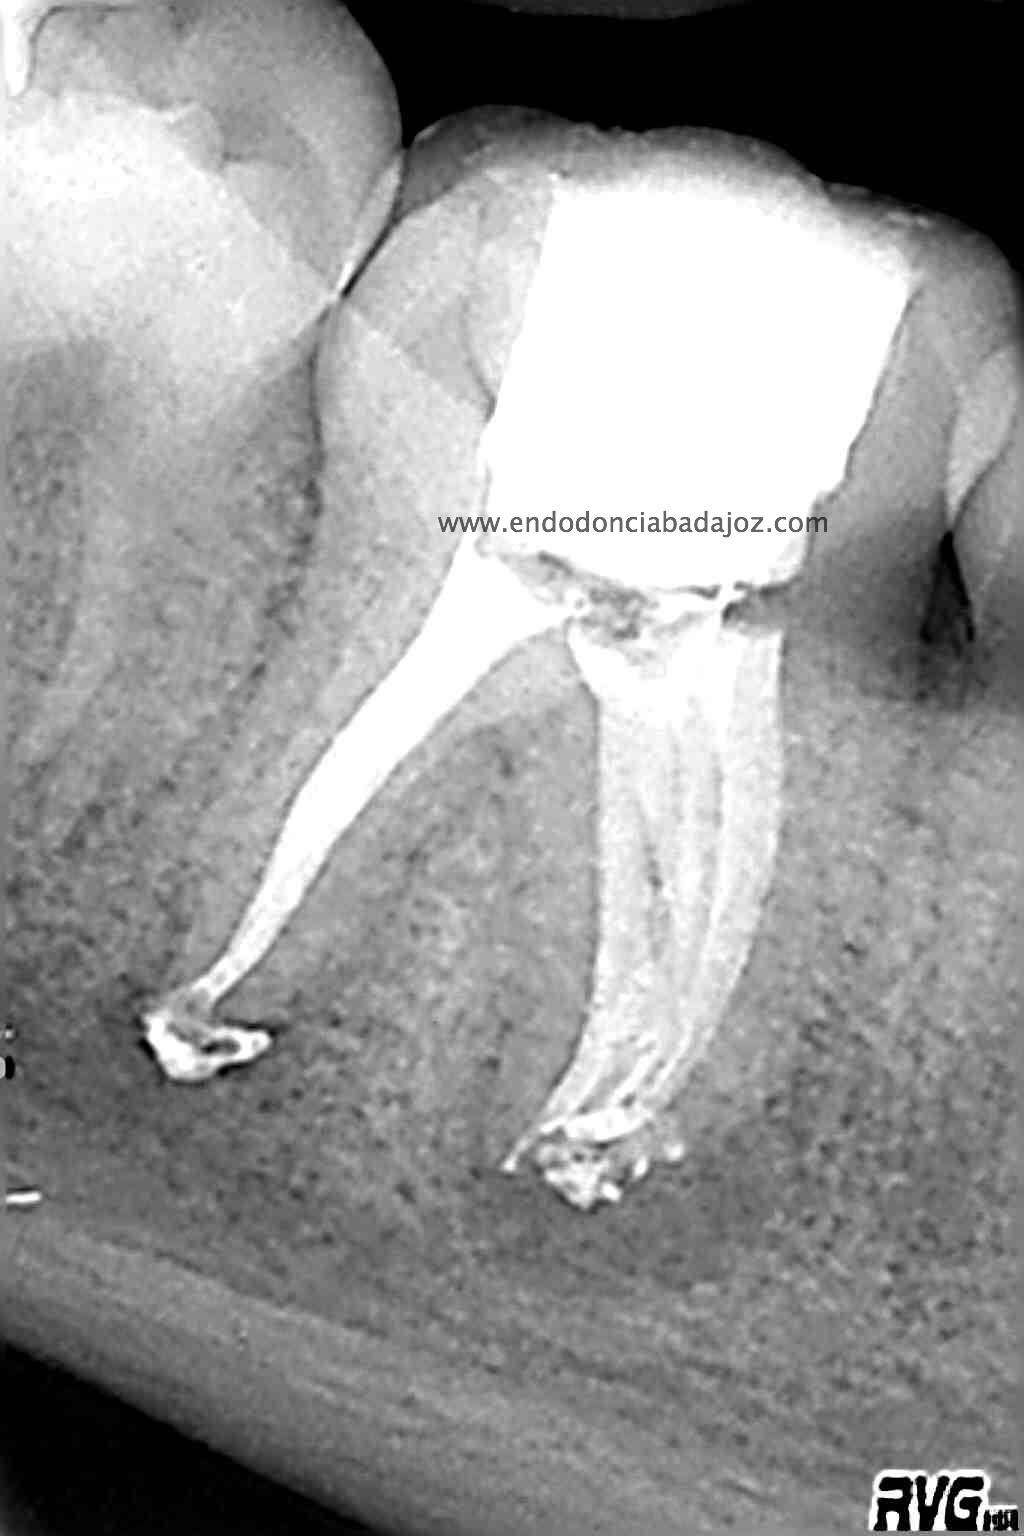

Llamamos a revisión 9 meses después a nuestro paciente:

Con estas tres proyecciones nos quedamos mucho más tranquilos y seguros de un buen sellado hermético y tridimensional des sistema de conductos de esta pieza.